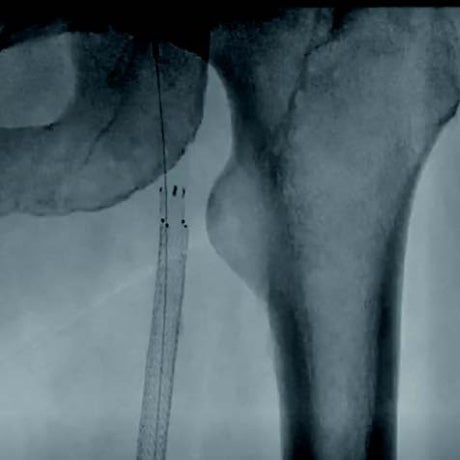

本症例は、初回治療2年後フォローアップ時のエコー所見から、DESの中枢および末梢の病変が閉塞の原因となった可能性が高い。同部位はDCBおよびDESで治療されているにもかかわらず、2年で再狭窄を呈していることから、drug technologyを用いたバルーンおよびステントでの治療は許容できないと判断した。BMI 31.9の肥満であったため右総大腿動脈より対側山越アプローチとした。6 Fr 45 cmガイディングシース + 5.5 Frシースバックアップ下に血管内超音波(IVUS)ガイドで臨んだ。エコー所見どおりDESの中枢および末梢病変は非常に強固であったため、ガイドワイヤー(40 g)で通過した。DES内の病変は非常に柔らかく、ガイドワイヤー(1 g)で通過、DCBのステント内閉塞はガイドワイヤー(15 g)を用い、IVUS下に確実に真腔内で通過した。0.014 inchガイドワイヤーの場合、ガイドワイヤーはステントストラットを容易に通過する。そのため、複数方向からの透視やIVUSを用いることで、確実にステント内を通過していることを確認することが必要となる。また、ステント内はhealthy landingではないことから、確実に前回のステントを最低1 cm以上越えて留置すべきである。DESの再狭窄は、culprit以外が柔らかい赤色血栓であることが多く、この症例もガイドワイヤーの感覚から同様の所見が疑われた。末梢塞栓予防に造影カテーテルによる可及的血栓吸引を行い、バルーン4.0 mm × 300 mmで前拡張をした。末梢病変はバイアバーン® ステントグラフト6 mm × 150 mmを留置、中枢は左浅大腿動脈起始部から10 mmのhealthy landingが残存していたため、同部位よりステントグラフト6 mm × 150 mmを留置した(図1)。高耐圧バルーン6.0 mm × 150 mmで後拡張を行い(図2、図3)、十分にgainを確保し良好なflowで終了した。治療時間は40分、造影剤使用量は70 mL であった。